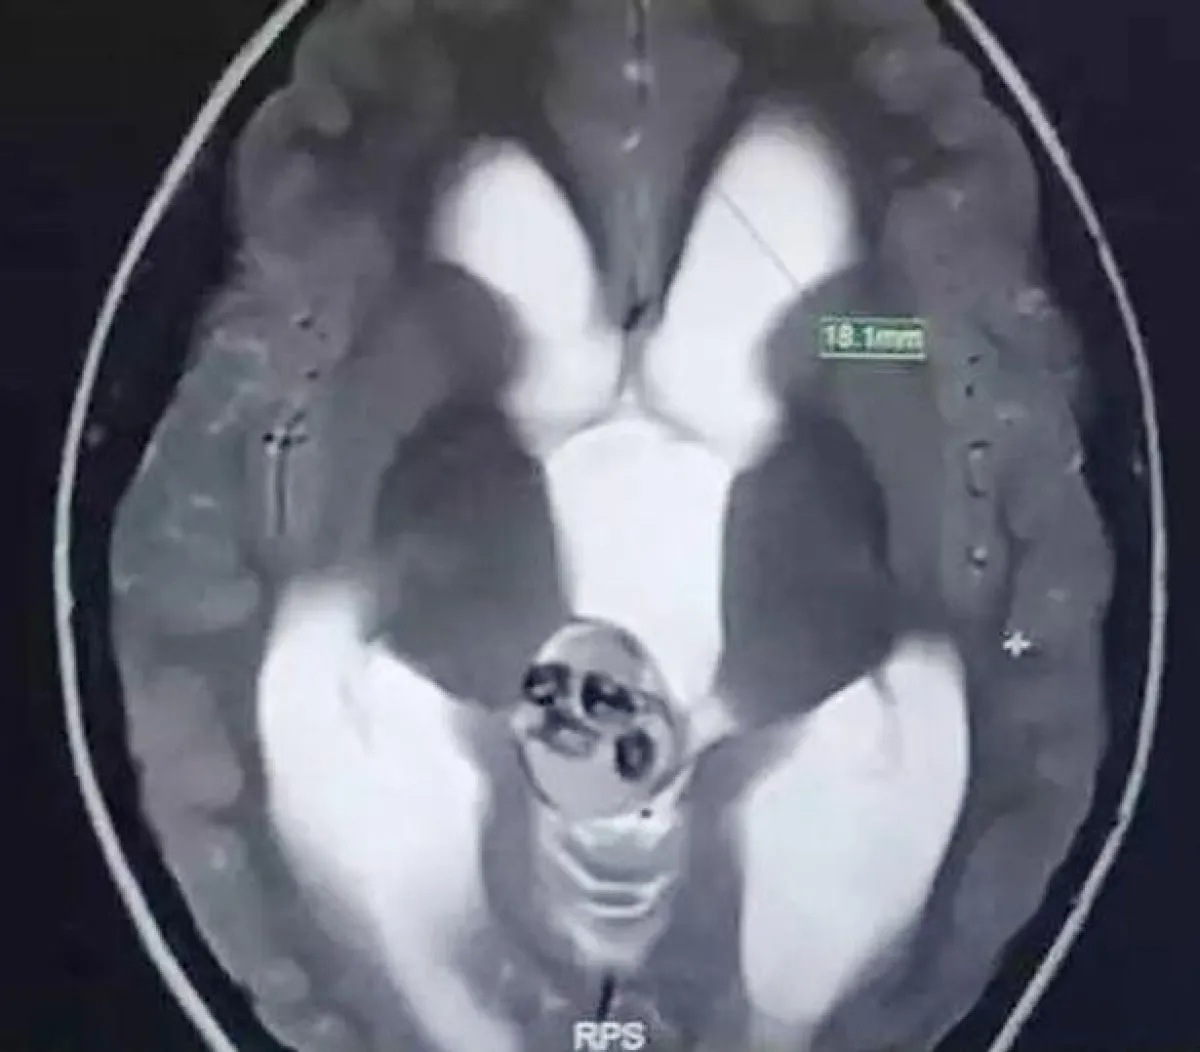

في واقعة طبية غريبة، عثر أطباء بمستشفى الأطفال في جامعة تشجيانغ، شرق الصين على حوالي 9 أسنان، داخل دماغ طفل عمره 5 سنوات.

وأشار الطبيب إلى أن حالة الطفل الغريبة، ناتجة من ورم نادر، لم يتم اكتشافه منذ ولادته، موضحًا أن ذلك الورم أدى لتشكيل هياكل عظمية من الأسنان داخل دماغه. بحسب صحيفة «ميرور»